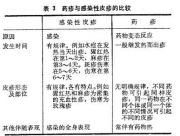

| 2021年7月26日 (一) 20:03 | 药疹与感染性皮疹的比较.jpg (文件) |  |

45 KB | Uploaded with SimpleBatchUpload | 3 |